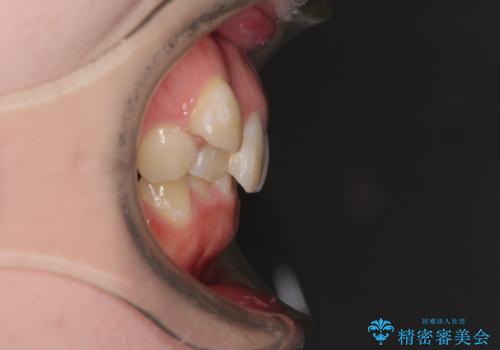

- 八重歯と下顎小臼歯の欠損を気にして来院された患者様です。

下顎小臼歯の欠損により過蓋咬合となっていたため、下顎は臼歯を起こすことで咬み合わせを改善し、八重歯は第一小臼歯2本を抜歯し、補助装置を使用して速やかに改善することとしました。